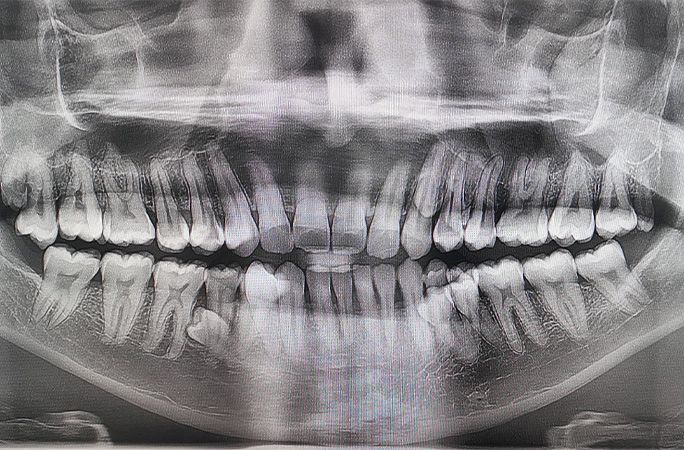

Společně je tehdy spočítali a našli celkem 38 zubů. Následné rentgenové vyšetření ukázalo, že další čtyři zuby teprve čekají na prořezání. Na začátku roku 2023 tak bylo jasno - celkový počet se ustálil na čísle 42.

Na prořezání dalších dvou zubů stále čeká.

Rekord byl následně potvrzen po vyšetření dvěma zubaři. Překvapivé přitom je, že většina lidí si jeho odlišnosti vůbec nevšimne. „Lidé jsou obvykle velmi překvapení a často tomu zpočátku ani nevěří,“ říká Muniandy.